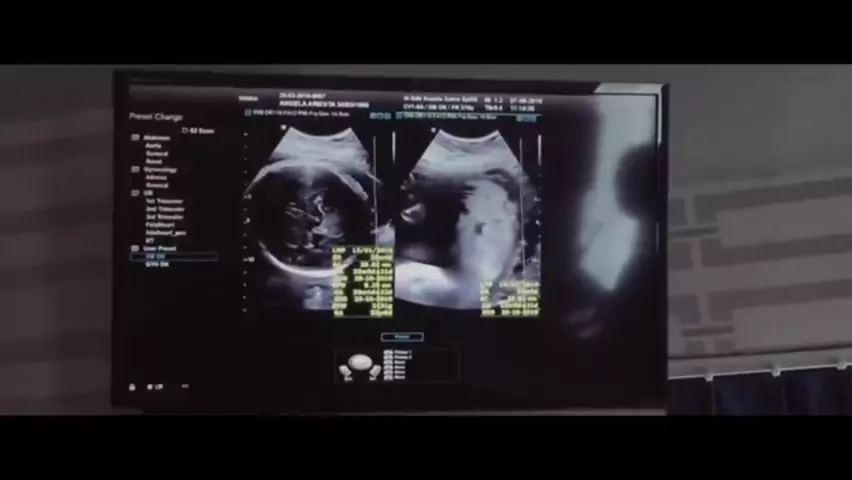

Sampai ketemu di surga lentera ku Papi &Mami Selalu mencintaimu tanpa batas waktu #like4like#likeforlike#tagforlike #tagsforlikes#liker#likers#tagsforfollo #tagforfollow#likeforlike#tagforlike#tagsforlike #likers#tagsforfollow#tagforfollow#instafollow #instagood#fyp #follor4follow#instalike4app #followme#beautiful#swag#tagforlove#like